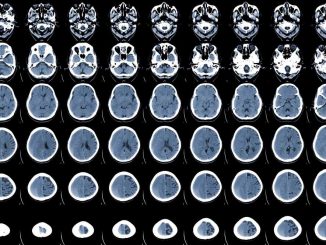

How SARS-CoV-2 infection affects acute ischemic stroke outcomes

03.06.2023

The ongoing coronavirus disease 2019 (COVID-19) pandemic, caused by severe acute respiratory syndrome coronavirus-2 (SARS-CoV-2), has affected millions of individuals […]